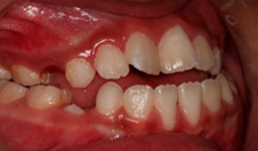

EJEMPLOS:

A) Maloclusión por mandíbula pequeña.

B) Maloclusión por mandíbula grande.